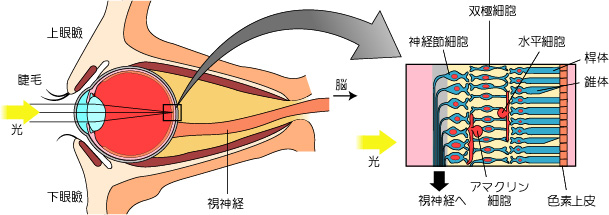

眼の発生と解剖・機能 (専門医のための眼科診療クオリファイ。眼の発生と解剖・機能 (専門医のための眼科診療クオリファイ。目の解剖学(概要) | 眼精疲労治療 難聴めまい肩こりは東京都北区。眼の構造と機能に関する専門的な知識を提供する書籍。健康・医学 Materia Poetica: Homeopathy in Verse。眼の基礎知識(2)。- 書籍タイトル: 眼の発生と解剖・機能- 著者: 大藤哲郎- シリーズ名: 専門医のための眼科診療クオリファイ- 定価: 定価本体20,000円(税別)ご覧いただきありがとうございます。